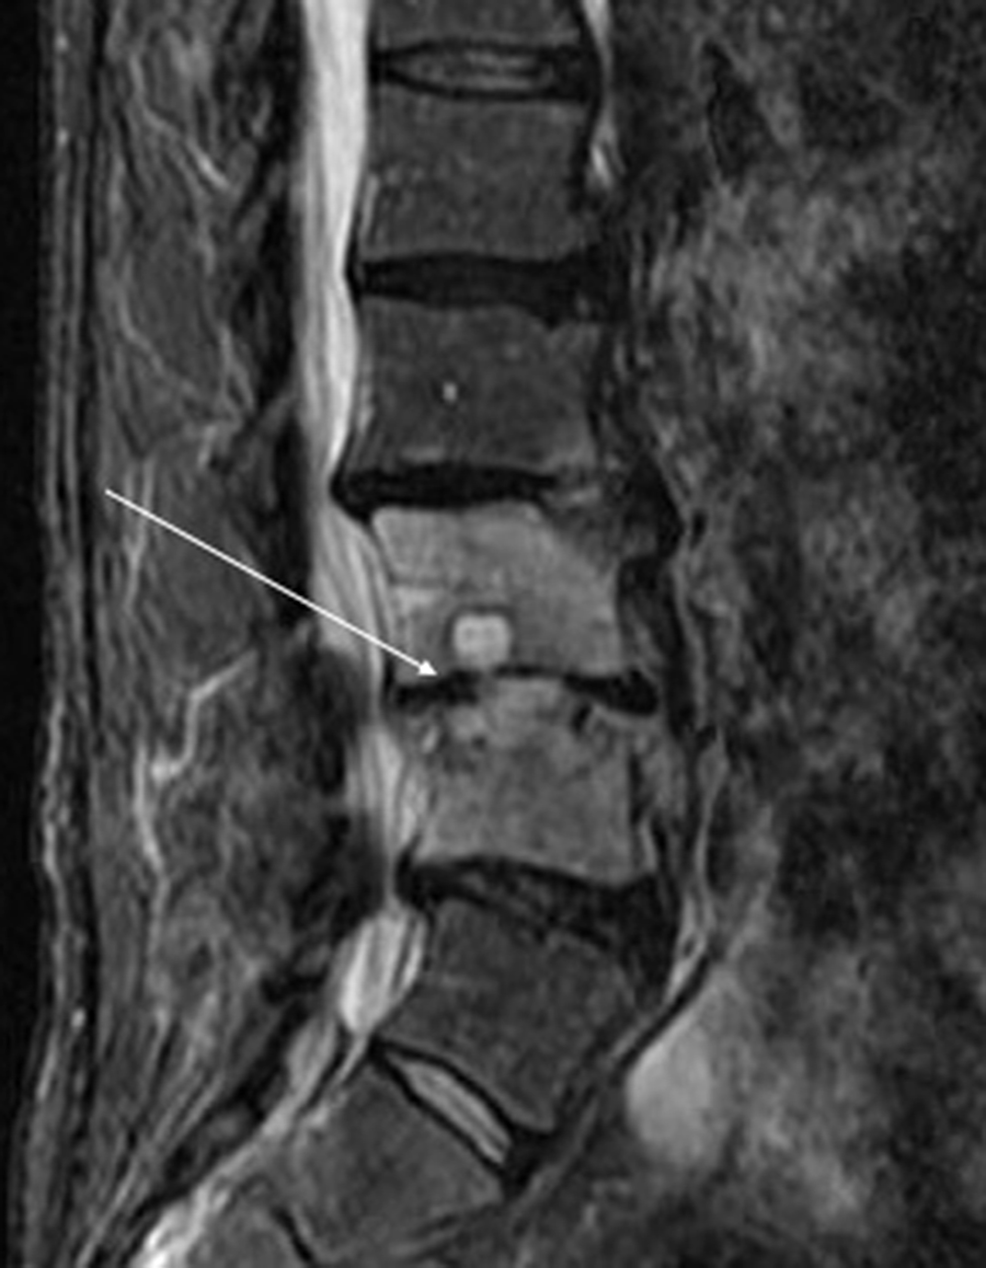

Plain radiographs revealed degenerative changes without evidence of fracture (Figure 1). Magnetic resonance imaging (MRI) raised the suspicion of osteomyelitis involving L2-3 and L3-4 with a possible abscess in the L3-4 disk space (Figure 2). A computerized tomography (CT)-guided biopsy provided tissue which registered positive cultures for Candida glabrata resistant to fluconazole, itraconazole, and posaconazole, but sensitive to micafungin and amphotericin B. No anaerobes, acid-fast bacilli, or aerobic organisms were present in the bioptic material.